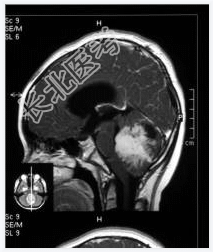

- [材料题] 患者,男性,10岁,因头晕、头疼伴呕吐1月,加重2天入院。做头颅MRI检查。

- 简答题1、诊断及依据是什么?

- 简答题2、鉴别诊断有哪些?